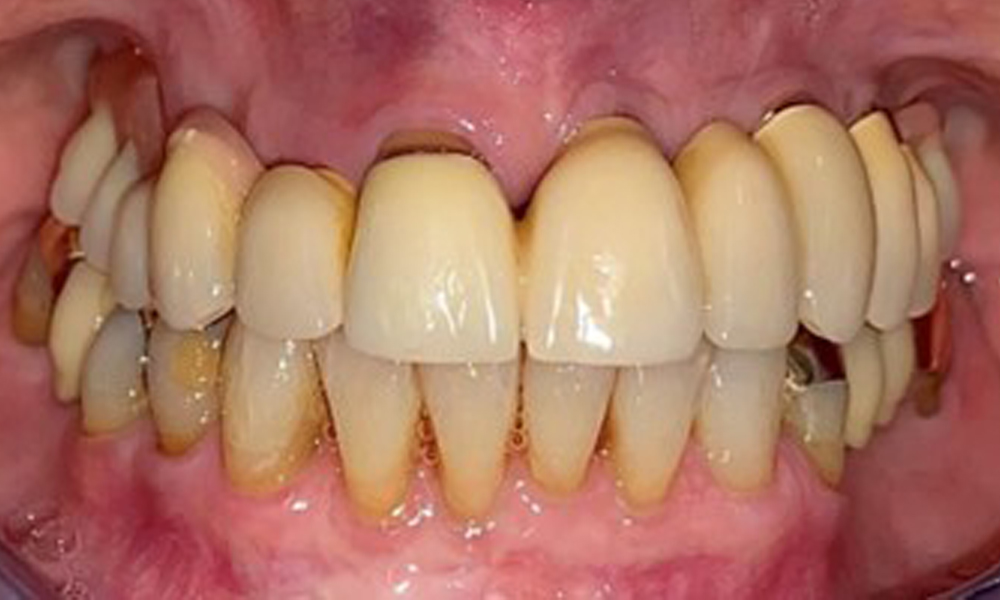

The patient was fitted with a combined removable maxillary telescopic prosthesis more than 25 years ago (Fig. 1, Fig. 2, Fig. 3) and is very happy with her dentures. The patient has an adequate fixed denture for the mandible (Fig. 4).

Frontal view with the maxillary denture in situ.

Fig. 1: Frontal view with the maxillary denture in situ.

The dental findings are as follows: Combined removable implant and tooth-supported telescopic prostheses on implants 15, 13, 21, 23, 24, 25 and tooth 11 (Fig. 1, Fig. 2, Fig. 3). The patient was fitted with a fixed mandibular denture. Adequate bridges were present over 37 to 34 and 45 to 47 (Fig. 4), the crown margins were intact and there were no active caries. A composite filling with a marginal gap was present on tooth 43. There was mandibular gingival recession, exposing 1 to 3 mm of root surface. This also applies to 11.

Periodontal findings

The periodontal condition remains stable. There was no gingival or peri-implant soft tissue inflammation. At 1 to 3 mm, the probing depths were within the physiological range. There are generalised recessions measuring 1 to 3 mm. Implant 23 has an increased probing depth of 4 mm, although there are no signs of secretion or bleeding (Fig. 6). The total BOP is 12%.